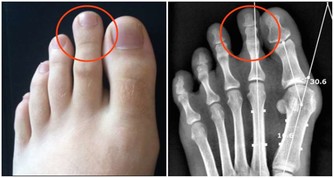

信號五:腳趾甲異常

△健康徵兆:

1、趾甲厚重發黃:可能由於黴菌感染而引起,糖尿病患者、有循環問題和免疫系統問題的人容易感染該疾病;

2、趾甲有凹痕:可能由於微量元素缺乏所引起,也有可能是其他疾病,

如牛皮癬關節炎,表現為指甲有很多小洞,可深可淺。